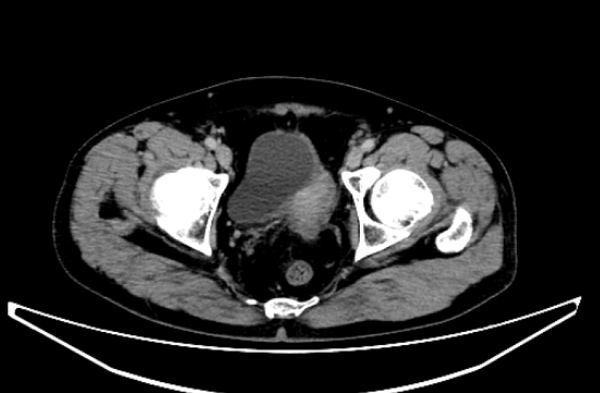

腹腔镜下左侧半尿路切除+全膀胱切除+淋巴结清扫术+右侧输尿管皮肤造口术(四级手术):在特聘专家南昌大学第一附属医院王共先教授指导下,我院泌尿外科团队为一名经术前活检确诊膀胱及左侧输尿管下段高级别浸润性尿路上皮癌且伴左肾重度积水失功的男性患者,成功实施了腹腔镜下左侧半尿路切除+全膀胱切除+盆腔淋巴结清扫术+右侧输尿管皮肤造口术。手术一次性完整切除双病灶,实现肿瘤根治的同时,兼具创伤小、出血少的优势,有效保障患者术后生活质量。此次手术的成功,再一次彰显王共先教授名医工作室技术帮扶与引领的显著成效。